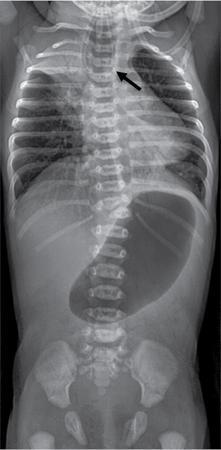

C.V. Kanimozhi, S. Muralinath, Raveendran J. Many of the important congenital gastrointestinal abnormalities present acutely in the newborn; some present much later. These include obstructive gastrointestinal lesions that present with vomiting, abdominal distension and not having passed meconium. The imaging modalities that are most commonly used in the evaluation of neonatal gastrointestinal abnormalities are plain films, contrast studies and ultrasound. Plain films remain a valuable tool in the assessment of abdominal abnormalities in the neonate. They are also an excellent guide to determining the next proper imaging study to perform for a particular problem. Certain neonatal bowel disorders have a pathognomonic appearance on radiographs obviating the need for further imaging. The essential and basic view to be done at the bedside is the supine view of the abdomen. In the evaluation of abnormal intra-abdominal gas patterns, alternative decubitus views, prone and supine cross-table lateral views may be taken. Erect view is not utilized in neonatal practice at the bedside as it is impossible to restrain a neonate in that position and unnecessarily subjects the neonate to stress, which may worsen the condition of an already sick baby. Evaluation of the bowel gas pattern and the anatomic localization of the intra-abdominal gas is the key to diagnosis in the evaluation of diseases of the GI tract. The bowel gas in the neonate is essentially swallowed air (Box 7.8.1). Movement of Air Through the GIT in a Term Neonate Most infants pass meconium by 24 hours of life. In order to interpret the bowel gas pattern and determine if an abnormality is present, it is crucial to know the age of the neonate (hours since birth) at the time the radiograph was taken. When there is impaired swallowing, such as due to CNS depression or in prematurity, radiographs show diminished bowel gas. In cases of bowel atresia, radiographs show absence of bowel gas in distal segments. Thus, the distribution of bowel gas and its pattern serve as pointers to the diagnosis. After the radiograph has been done, depending on the findings, an ultrasound or fluoroscopic contrast study may be performed next. The radiologist should tailor the contrast study to suit the particular patient and the clinical question that needs to be answered. In cases of suspected high GI obstruction, an upper GI contrast series is study of choice; in cases of suspected low GI obstruction a contrast enema should be performed to delineate the anatomy. When performing fluoroscopic studies, it is important to bear in mind the radiation dose and to adopt the ALARA principle. Minimizing radiation exposure in children is important because they are more sensitive to the effects of radiation and have a longer life expectancy than adults. The technical parameters must be adapted to paediatric imaging. Ultrasound is a useful bedside tool particularly in the sick neonate. In neonates, the sonographic image resolution is excellent due to the lack of significant body fat. In neonates, exquisite images of the abdomen can be obtained with the high-resolution ultrasound probe, which permits imaging the bowel wall in great detail. In addition, it can also reveal other causes for abdominal distension or vomiting. In this chapter, we will discuss the aetiology, clinical presentation and imaging appearances of congenital neonatal gastrointestinal abnormalities. We will also discuss common acquired abnormalities that present in the neonatal period, namely necrotizing enterocolitis. Congenital oesophageal malformations of the newborn include the various types of atresia (with and without fistula) and oesophageal duplications. Oesophageal atresia with or without tracheoesophageal fistula (TEF) is a common congenital anomaly that manifests in the neonatal period. It is also the most important congenital malformation of the oesophagus. Oesophageal atresia is commonly associated with other anomalies of the gastrointestinal tract such as imperforate anus, pyloric atresia, duodenal atresia and annular pancreas and less frequently with anomalies of the cardiac and genitourinary systems. About 20% of patients with oesophageal atresia have the VACTERL syndrome (vertebral anomaly, anorectal atresia, cardiac lesion, tracheoesophageal fistula, renal anomaly, limb defect). Oesophageal stenosis and webs may be associated with oesophageal atresia. The aetiology of oesophageal atresia and TEF is not completely understood. Faulty separation of the primitive trachea and oesophagus is the most widely accepted theory. The way the primitive foregut cleaves into a ventral (tracheal) passage and a dorsal (oesophageal) passage is a complex process and is poorly understood. Folds developing from the longitudinal ridge is said to separate the two. When the separation has an extreme tracheal bias, an oesophageal atresia occurs and if the bias is towards the oesophagus, then a tracheal atresia ensues. Incomplete separation may result in fistula of various types. Oesophageal atresia and TEF are classified depending upon the absence or presence and location of the fistula between the oesophagus and the trachea (Fig. 7.8.1). Neonates present within a few hours of birth with excessive salivation, drooling, cyanotic spells and regurgitation of feeds. The inability to successfully pass a nasogastric tube strongly suggests oesophageal atresia. Newborns with H-type fistula may have feeding difficulties and choking, but often the presentation and diagnosis is only later in infancy when the patient presents with cough, choking episodes and recurrent pneumonia. The role of imaging is to diagnose, define the anatomy to the best extent possible and evaluate for other anomalies to provide a clear picture for the paediatric surgeon. For example, it is important for the surgeon to know the side of the aortic arch in order to lateralize the surgical approach. Chest X-ray and Echo can localize the arch and determine if an anomalous right-sided aortic arch is present. Plain films of the chest including abdomen need to be obtained. The radiograph will demonstrate the air-filled distended proximal oesophageal pouch. If a nasogastric tube has been inserted, the coiled tube will be seen within the pouch. Absence of bowel gas in the abdomen indicates oesophageal atresia without a distal fistula – types A and B have this radiographic appearance (Fig. 7.8.2). The presence of gas in the gastrointestinal tract indicates the presence of a distal fistula – types C and D (Fig. 7.8.3). Contrast studies to delineate the proximal pouch are generally not indicated. Coiling of the nasogastric tube in the proximal pouch confirms the diagnosis. Chest radiographs frequently show changes of consolidation due to aspiration pneumonia, most often involving the right upper lobe (Fig. 7.8.4). In cases of H-type fistula, plain films are nonspecific and the diagnosis depends on contrast studies. Radiological diagnosis is made by means of a tube oesophagogram. This study has the potential risk of aspiration and the neonate may desaturate quite rapidly. Hence, it is important to have neonatal emergency resuscitation at hand. The tube oesophagogram is performed under fluoroscopy with the baby in lateral- or steep-prone oblique position. The NG tube is placed at the oesophagogastric junction and is gradually withdrawn while simultaneously injecting contrast. Nonionic low-osmolar contrast agent should be used. Most of the H-type fistulas are located in the lower cervical and upper thoracic regions with the fistula typically coursing upward and forward from the oesophagus. In the presence of a fistula, the contrast will be seen passing into the trachea in an upwardly oblique configuration. Aspiration during the study can also cause the contrast to appear in the tracheal tree and the lungs. It needs to be established whether the contrast has passed through the fistula or whether aspiration has occurred. Recording of the fluoroscopic run and reviewing the images may be required to make this distinction. Repeat examination may be required. Demonstration of H-type fistula can be difficult radiologically. In such patients, bronchoscopy with transfistula guidewire placement has been found to be of use. MRI – High resolution structural MRI is a new technique that is being used to visualize tracheobronchial anatomy. The disadvantage with radiographs is that one cannot determine the anatomic subtype of TEF, the site of the TEF or the length of the gap between the atretic segments. Using ultrashort echotime (UTE) MR imaging, it is possible to visualize the exact site of the fistula and assess the size of the oesophageal gap. This can aid presurgical planning and help identify infants at risk for complications, such as those with a long oesophageal gap. Imaging plays an important role in the evaluation of early and late complications of atresia repair. Early complications include anastomotic leaks and are seen in about 10%–20% of cases. Oesophageal contrast study, using a nonionic low-osmolar contrast agent, is performed to demonstrate the leak at the anastomotic site (Fig. 7.8.5). Leaks are associated with a greater incidence of subsequent stricture development. Anastomotic stricture is a common complication seen in about 30%–40% of cases. Often there is a slight narrowing at the site of repair without the patient having any difficulty in swallowing (Fig. 7.8.6). The anastomotic narrowing is clinically relevant only if the patient has dysphagia; such cases respond to dilatations. Recurrent TEF occurs in 5%–10% of cases after oesophageal atresia repair. Late complications include dysphagia, gastroesophageal reflux, tracheomalacia and chest wall deformities. Dysphagia can occur post-operatively due to abnormal oesophageal motility. Oesophageal dysmotility can be caused by abnormal neural development of the oesophagus or may result from complication of atresia repair. Gastroesophageal reflux affects 40%–65% of patients following oesophageal repair. It may be due to an intrinsic deficiency in the motor function of the oesophagus; this may get exacerbated postrepair due to an alteration of the anatomical gastroesophageal junction. Oesophageal atresia key imaging finding – X-ray shows NG tube coiled in proximal oesophageal pouch. The stomach is divided into the fundus and body proximally and the antrum distally. The antrum is divided by the sulcus intermedius into a proximal pyloric vestibule and a distal pyloric antrum or pyloric canal. This canal terminates into the pyloric sphincter beyond which is the duodenum. Congenital anomalies of the stomach that manifest in the neonatal period are uncommon. Hypertrophic pyloric stenosis (HPS) is the most common surgical cause of vomiting in infants. The incidence is 2–5 per 1000 live births, with geographic and racial variations. Compared to Caucasians, HPS is less common amongst Asian populations. The male to female ratio is approximately 4:1, occurring more commonly in the first-born child. The precise aetiology is unknown. Overactivity or prolonged spasm of the circular muscle of the pyloric antrum is thought to be the primary problem in these infants. This spasm leads to muscle hypertrophy and obstruction. Multiple hypotheses have been proposed for this prolonged spasm. One is that some infants are genetically predisposed to increased gastrin production which leads to a vicious cycle of hyperacidity, increased gastric contraction and secondary development of muscular hypertrophy. Most infants present after the first week of life and before 3–4 months of age. Typical symptoms include projectile nonbilious vomiting, regurgitation and difficulty in feeding. The gastric outlet obstruction can lead to emaciation. The distended stomach with active peristaltic activity may be visible through the thin abdominal wall. In the past barium upper GI series was the mainstay diagnostic tool for HPS. Prior to the barium study, the stomach may need to be decompressed via a nasogastric tube. The classic sign on a barium study is the ‘string sign’ (Fig. 7.8.7) produced by a thin stream of barium in an elongated narrowed pyloric canal; the canal typically curves upward. In severe cases, complete obstruction will lead to the ‘beak sign’, which is produced by beaking of the contrast as it enters the pyloric canal. With lesser degrees of obstruction, the ‘double track sign’ is seen. This is produced when the pyloric canal is flattened and the barium accumulates in the crevices along either side of the flattened canal. Pylorospasm can transiently mimic the findings of HPS. Currently, ultrasound is the modality of choice for the diagnosis of HPS and upper GI studies are seldom used. Ultrasound is considered the ‘gold standard’ as it allows direct examination of the pyloric muscle and also provides the ability to perform a dynamic study. The ultrasound examination is performed with a linear high-frequency transducer (6–10 MHz). The examination begins with the baby in supine position. First, the antropyloric region is identified; the pylorus is usually located medial and posterior to the gall bladder. The normal pyloric muscle is a thin hypoechoic layer that measures 2 mm or less. The abnormal pyloric canal shows thickening of the muscle and the mucosa to varying degrees. In cross section, it is seen as a hypoechoic structure likened to a doughnut. The length of the canal is measured in long section where its appearance is likened to the cervix. The sonographic diagnostic criteria for HPS are a thickened muscle layer measuring ≥3 mm and an elongated pyloric channel ≥15 mm (Fig. 7.8.8). The diameter of the pylorus in cross section was also one of the originally used measurements. However, due to a significant overlap between normal and abnormal, this measurement is no longer utilized. Additional ultrasound findings of HPS are hypertrophy of the pyloric mucosa and a distended, actively peristalsing stomach. The hypertrophied redundant mucosa projects into the antrum analogous to the ‘nipple sign’ in barium studies (Fig. 7.8.8D.). Colour Doppler imaging shows increased flow in the muscle and mucosa. The above-described measurements of pyloric muscle thickness and canal length are vital to diagnosis. However, dynamic assessment is equally important. One must evaluate the antropyloric region over a period of time to ensure persistent stenosis without evidence of relaxation and opening of the canal. A distensible antropyloric region with normal passage of gastric contents excludes HPS. Transient contractions of the pylorus or pylorospasm can mimic pyloric stenosis in both measurement and appearance. With observation over a period of time, opening of the pyloric canal may be visualized. Hence the key to diagnosis of HPS is persistent non-relaxing thickened musculature. Gas in the stomach may obscure the pylorus. To avoid this, place the infant in an oblique position, right side down which will allow the antrum to fill with fluid. Conversely, an overdistended fluid-filled stomach can displace the pylorus dorsally. In such cases, turning the infant left side down will displace the fluid towards the fundus and will allow the pylorus to rise to a more anterior position. At times, equivocal examinations may occur where the muscle measures 2–3 mm in thickness and does not relax. In these patients, careful monitoring with repeat ultrasound is warranted. In a few cases, the abnormalities advance overtime to fully developed HPS. Hence in such equivocal cases if vomiting continues, follow-up ultrasound is advisable. Surgical pyloromyotomy is the treatment for HPS. On ultrasound, the myotomy site can be seen as an interruption in the hypoechoic doughnut. It is important to be aware that postsurgery, the pyloric muscle may remain thickened for up to 5 months with a gradual return to normal thickness. In the first week after surgery, the muscle can be the same thickness as pre-op or even thicker. One should not be alarmed by this appearance. The dimensions gradually return to normal over the course of a few months. Postop if the child is thriving well, there is no need for imaging to be performed. HPS key imaging finding: On high-frequency ultrasound muscle thickness ≥3 mm and elongated pyloric channel ≥15 mm. Pyloric atresia is a rare anomaly comprising less than 1% of all intestinal atresias. Pyloric atresia is classified into three types (Fig. 7.8.9): The exact aetiology remains controversial. In the past, it was postulated that failure of recanalization of the gastrointestinal tract was the cause. Recent evidence suggests that pyloric atresia is the result of localized vascular occlusion. This vascular theory suggests that the atresia is due to focal ischemia secondary to intrauterine stress, vascular insult or anoxia. In complete obstruction, the presentation is in the neonatal period with nonbilious vomiting within the first few hours of life. Incomplete obstruction due to a diaphragm has a variable presentation depending on the size of the orifice. These patients can present later in life with intermittent vomiting or postprandial vomiting. In complete pyloric atresia, a dilated stomach is present on radiographs with absence of gas in the distal bowel. This is known as ‘single bubble’ appearance (Fig. 7.8.10). This appearance is diagnostic and in such cases, contrast studies are generally not required. In the membranous type, there is an opening in the centre of the diaphragm and hence, the obstruction is usually incomplete. On radiographs, the stomach is distended and lesser than normal volumes of air is present in the small bowel (Fig. 7.8.11). On upper GI barium studies, a diaphragm is seen as a thin (2–4 mm) linear filling defect that spans across the antrum with a normal pyloric canal. One needs to determine on fluoroscopy whether the membrane is causing significant obstruction or not. If obstructing, the diaphragm will balloon out with gastric peristalsis. In incompletely obstructing diaphragms, the edges of the diaphragm will be visible but there will no obstruction or ballooning. Pyloric atresia key imaging finding: X-ray abdomen – ‘single bubble’ appearance. Microgastria is an extremely rare congenital abnormality wherein the stomach is small, midline in position and typically associated with a dilated oesophagus. The stomach is represented by a small tubular structure without recognizable differentiation into fundus, body, antrum and pylorus. Agastria is the most extreme form of microgastria. Microgastria is frequently associated with other anomalies such as polysplenia-asplenia syndrome, malrotation, gastrointestinal atresia and vertebral, cardiac, renal and limb reduction anomalies (VACTREL association). Microgastria occurs due to arrest in early development of the foregut. In the 5th week of gestation, dilatation of the region of the future stomach occurs. Ninety-degree rotation of the stomach occurs in the 6th week, followed by development of the greater and lesser curves and growth of the fundus in the subsequent weeks. Arrest of this process leads to microgastria, with severity dependent on the stage at which arrest occurs. The development of spleen within the dorsal mesogastrium of stomach explains the association of microgastria and splenic anomalies. The association of limb, cardiac, tracheoesophageal, vertebral and renal anomalies has been attributed to impairment of early mesodermal development. The symptoms are related to the effects of the inadequate stomach and dilated oesophagus or due to the associated severe anomalies. These babies may present with feeding difficulties, failure to thrive, vomiting, recurrent aspiration and malnutrition due to severe gastroesophageal reflux. Radiographs may show an absent stomach bubble; in some cases, the shadow of the dilated oesophagus may be seen in the lower chest. On an upper GI study, the stomach appears small, tubular and midline in position. There is often associated severe gastroesophageal reflux and a very dilated oesophagus. The oesophagus dilates to take over the storage function of the inadequate stomach. Additional imaging studies are required to identify the associated anomalies. Key imaging finding: Upper GI study – Small, tubular stomach located in the midline. Congenital anomalies of the duodenum present with obstructive symptoms. The primary considerations for bilious vomiting in the neonate are duodenal atresia, duodenal stenosis, annular pancreas and malrotation with midgut volvulus. The most important investigation in the majority of these patients is an upper GI series as it accurately demonstrates the level and nature of duodenal obstruction. Duodenal atresia may be seen in isolation or in the setting of trisomy 21 (about 30% of patients have Down’s syndrome). Associated anomalies are frequent and include malrotation, oesophageal atresia, annular pancreas, biliary atresia, congenital heart disease and vertebral anomalies. Duodenal atresia is due to failure of gut recanalization during embryologic development leading to complete obstruction. Normal recanalization of the duodenum occurs between the 9th and 12th weeks of gestation. Failure of this process results in duodenal atresia. In most cases (roughly 80%), the atresia is distal to the ampulla of Vater. Neonates with duodenal atresia present with bilious vomiting in the first few hours of life. In those patients where the atresia is proximal to the ampulla, the vomitus will be nonbilious. In duodenal atresia, air is present in the stomach and duodenum with no gas in the distal intestinal tract. Dilatation of the stomach and the duodenum produces the characteristic ‘double bubble’ appearance on radiographs (Fig. 7.8.12). This appearance is diagnostic and rarely requires further imaging. Key imaging finding: X-ray abdomen – ‘double bubble’ appearance Duodenal stenosis and duodenal web cause partial obstruction due to a narrowed segment or thin membrane, respectively. As with duodenal atresia, both these conditions show a strong association with malrotation, annular pancreas and a preduodenal portal vein. Duodenal web and stenosis is due to incomplete recanalization of typically the second part of the duodenum. In babies with duodenal stenosis, the presentation and clinical findings depend on the degree of stenosis. Those with less severe forms of stenosis may present later in life. Radiographs in duodenal stenosis and web show a distended stomach and duodenum. Since the obstruction is incomplete, gas will be present in the distal loops. On upper GI study, duodenal stenosis is seen as a focal narrowing in the second part of the duodenum (Fig. 7.8.13). In duodenal web, a thin membrane/diaphragm is seen that partially obstructs the lumen, usually in the second segment of duodenum. The membrane is often difficult to demonstrate (Fig. 7.8.14). A ‘windsock deformity’ may also be seen; this appears as a proximal dilated duodenal segment with contrast outlining a thin web that bulges into a distal nondilated segment. This windsock duodenum is seldom seen in the neonatal period as this appearance is due to stretching of the membrane over time. Key imaging finding: Upper GI study – narrowing in second part of duodenum. Annular pancreas is an anomalous band of pancreatic tissue that encircles the second portion of duodenum. Annular pancreas may result in extrinsic duodenal obstruction. Often there is associated intrinsic duodenal abnormality viz. some degree of duodenal atresia, web or stenosis. As in duodenal atresia, associated anomalies such as trisomy 21, cardiac defects, malrotation, oesophageal atresia and anal atresia can occur. The pancreas arises as two endodermal outgrowths, ventral and dorsal buds, from the duodenum. The head of the pancreas derives from the smaller ventral bud. Annular pancreas occurs if the ventral bud becomes tethered to the duodenum or it fails to rotate completely before fusion with the dorsal bud. The clinical presentation is similar to duodenal atresia or stenosis. If the obstruction is complete, presentation is in the neonatal period with bilious vomiting. Cases of incomplete obstruction may remain asymptomatic until adulthood. Annular pancreas is the second most common condition to produce a ‘double bubble’ appearance on radiographs. Plain films will show dilatation of the stomach and duodenum. Upper GI contrast study will show narrowing of the second part of duodenum (Fig. 7.8.15). On ultrasound pancreatic tissue may be seen encircling the second part of duodenum (Fig. 7.8.16). At times the appearance may resemble a mass at the level of head of pancreas.